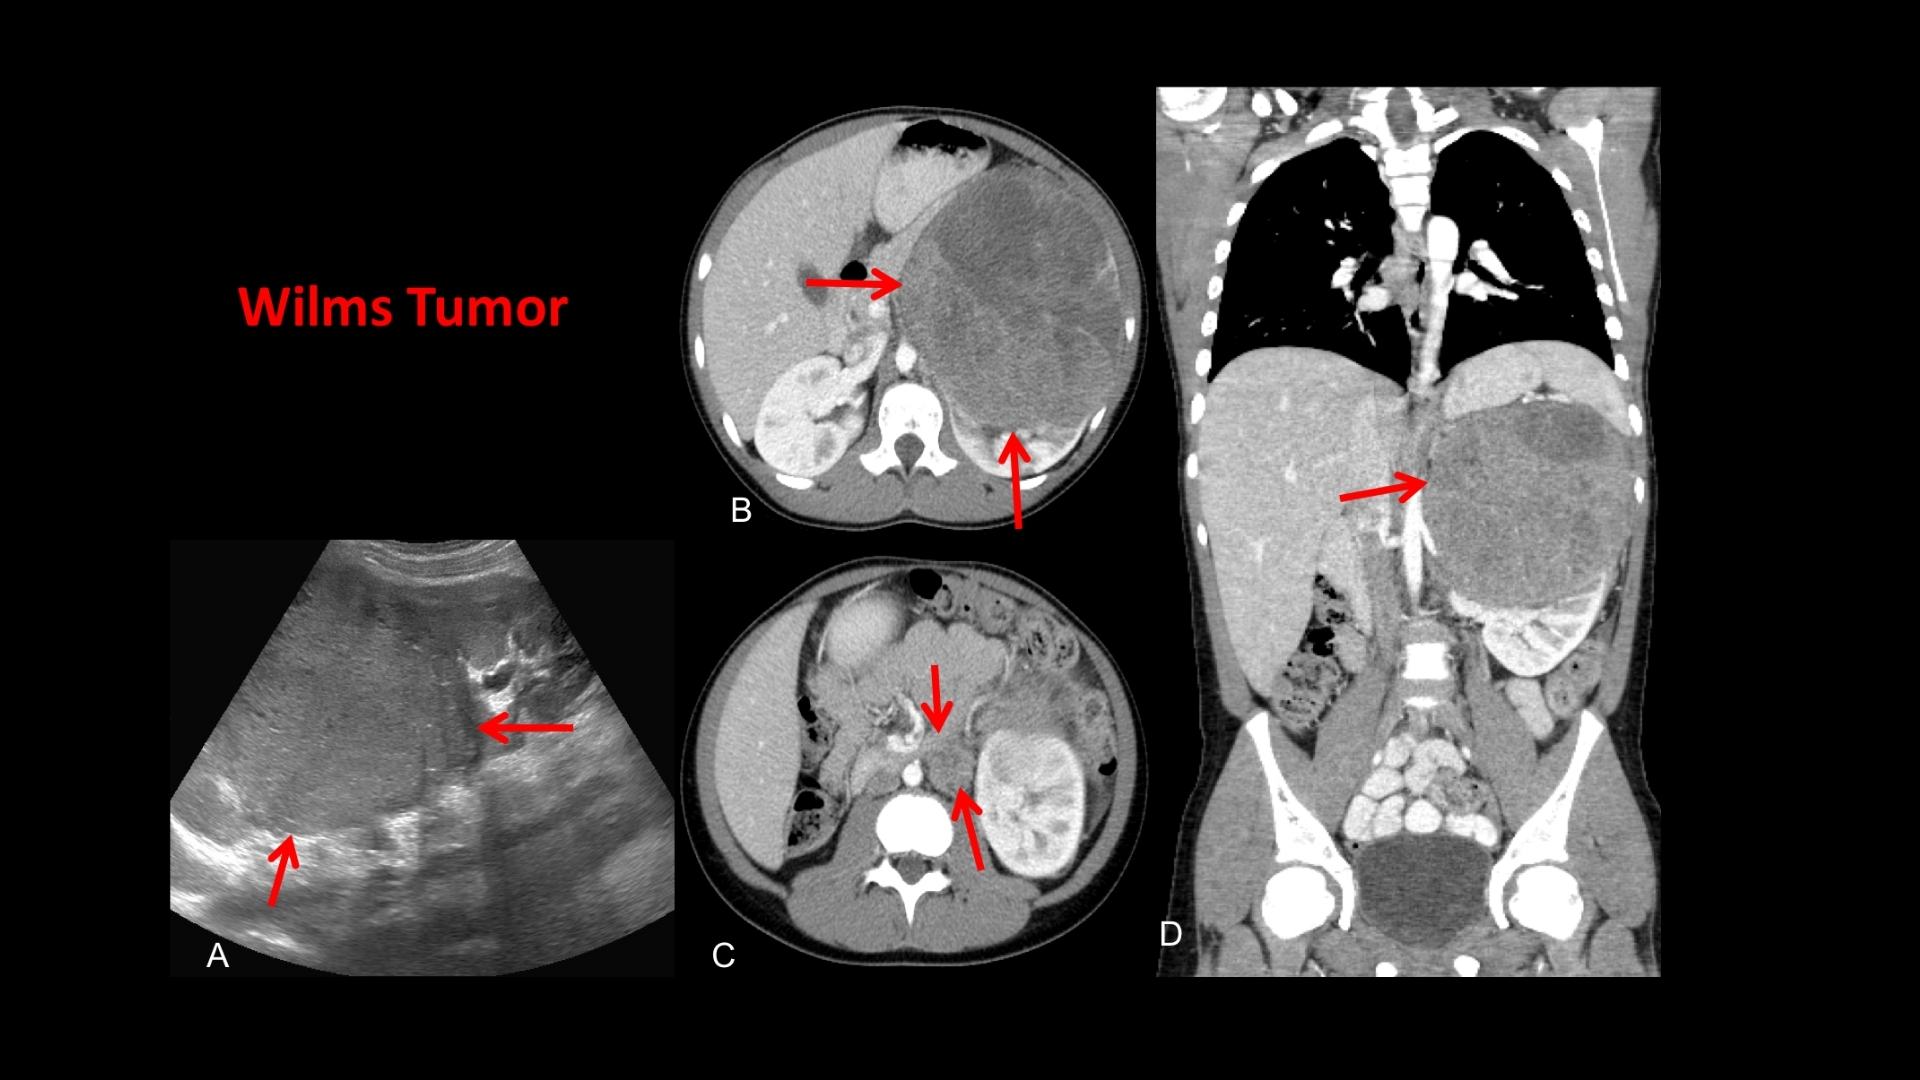

什麼是 Wilms 腫瘤(腎母細胞瘤)?

Wilms 腫瘤(腎母細胞瘤) Wilms 腫瘤 (腎母细胞瘤) 是一種罕見但可治療的兒童腎臟癌症,主要影響 3-4 歲的兒童,但偶爾也會診斷出年紀較大的兒童,成人則很少見。了解 Wilms 腫瘤 (腎母细胞瘤) 首先要知道它的生理基礎,即未成熟腎細胞的異常生長。